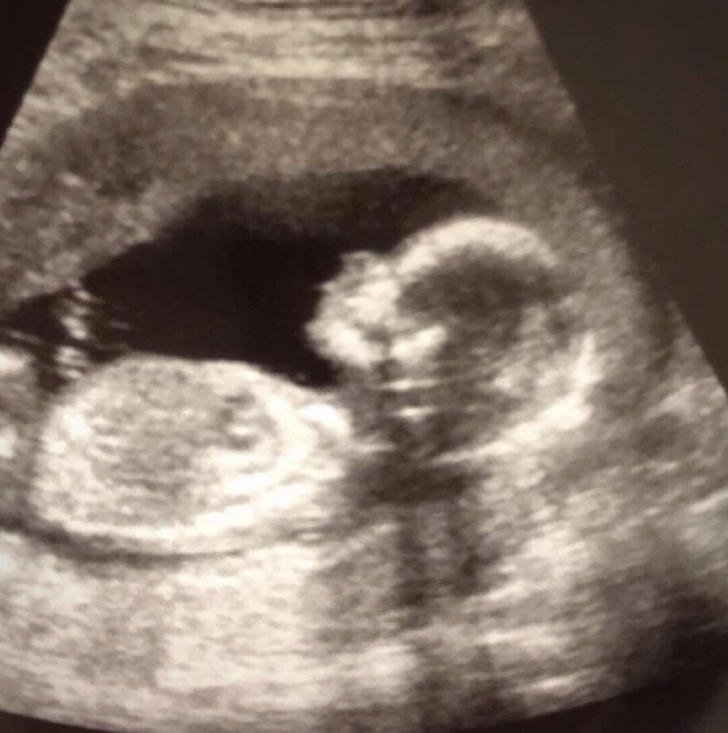

De zwangerschap bracht vreugde en spanning, terwijl ze zich voorbereidden op de komst van Kailor. Tijdens een echo zagen ze een gezond bewegend kindje, wat hun geluk vergrootte.

Jessica kreeg de diagnose subchorionisch hematoom, wat ernstige zorgen met zich meebracht, maar gelukkig was de baby gezond en ontwikkelde zich normaal.

Deze aandoening komt zelden voor, maar vereiste nauwkeurige monitoring en zorg. De artsen gaven advies voor rust en gezonde gewoonten om de zwangerschap te ondersteunen.